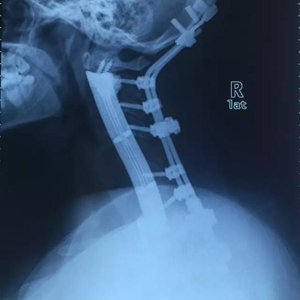

术后,在X光片里,小雯脑袋和身体之间的连接是前后两段金属。其中,作为主力支撑的3D钛合金假体14厘米长,有着可以察觉的曲度。

小雯术后的X光片

上海长征医院骨肿瘤外科的肖建如是这次手术的主刀。8月7日,在位于上海长征医院的办公室里,肖建如拿出小雯术后的X光照片,忍不住对澎湃新闻(www.thepaper.cn)说:“这个术后照片很漂亮。”